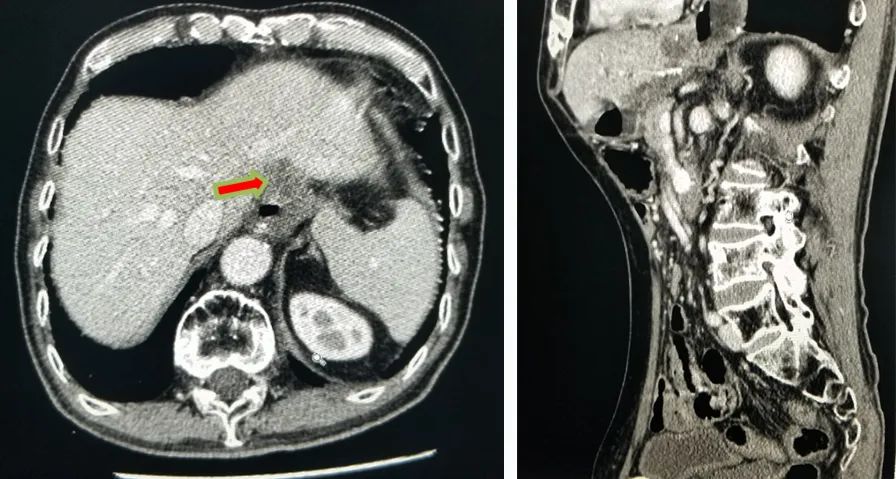

2020-01-08复查腹部CT:与患者前片(2019-7-8)比较显示:食管胃吻合口区低密度病变范围较前缩小。所示腹部其余病变较前未见明显变化,双肺片状高密度影,双侧胸腔积液。

△2020.01腹部CT

2020-08-31复查腹部CT:与患者前片(2020-1-8)比较显示:所示腹部病变较前未见明显变化。双肺高密度影范围较前缩小。

△ 腹部CT 2020.08